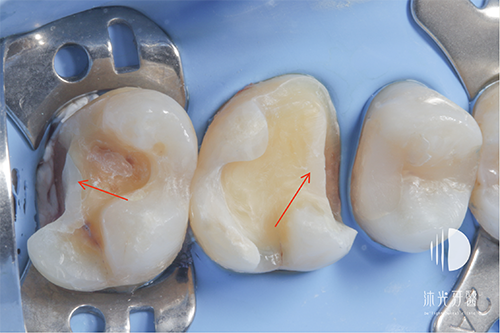

移除蛀牙

7